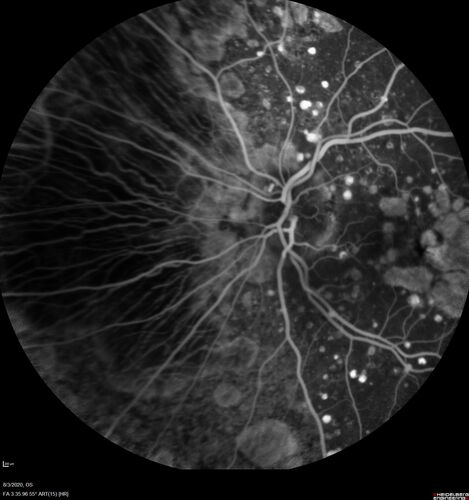

Dry AMD geographic atrophy and cystoid macular edema

79 year old vision is in for a checkup with no visual complaints in the left eye.  This is her better eye.  VA 20/200 OD, 20/50 OS.  3 years ago she had a CRVO in the left eye.  She is also diabetic for 20 years, has carotid insufficiency and anemia.  Left eye shows CME.  This was not treated and the vision improved to 20/40 over the next year although mild edema persisted.